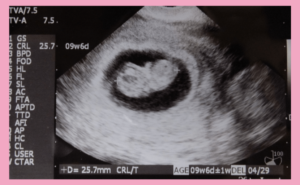

妊娠9週目の母体の変化とエコーでわかるダウン症の兆候【医師監修】…